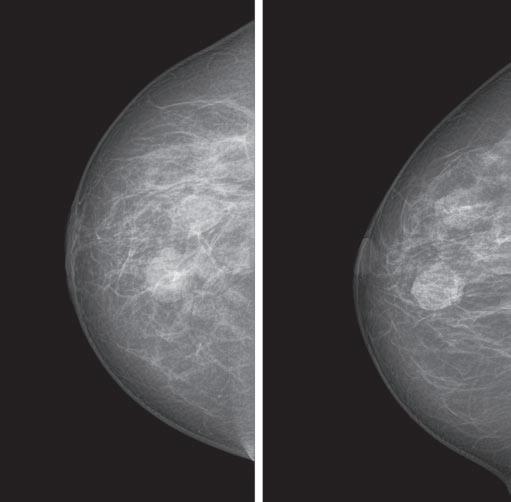

A yearly mammogram is the gold standard for breast cancer screening and detection. Mammography is the only test that has been scientifically proven to save lives. Still, it’s not infallible.

“In women with very dense breasts, mammography will miss cancer 58% of the time,” says Thomas Kolb, M.D., a breast cancer radiologist.

Dense breasts contain more glands, ducts, and connective tissue than fat. Breasts tend to be denser during a woman’s reproductive years. Density makes it harder to detect suspicious lumps on a mammogram; that’s because glandular tissue appears white on a mammogram, just like a mass can.

The latest in breast cancer detection technology, tomosynthesis, also known as 3D mammogram, is a digital mammogram that takes images of the breast in thin slices from multiple angles.

Tomosynthesis takes an arc of pictures through each breast, in 5-millimeter slices, which are then reconstructed into a three-dimensional image.

It allows radiologists to see through the breast tissue so they can more easily distinguish a true

Compared to a digital (2D) mammogram, tomosynthesis is more precise. Studies show that three more women per thousand will receive a cancer diagnosis with tomosynthesis, compared to a digital mammogram.

tomosynthesis, or 3D mammogram, takes images of breast tissue from multiple angles.

Also, women with dense breasts who undergo tomosynthesis are 40% less likely to be called back for additional imaging.

Should you ask for it? Screening tomosynthesis is in order if you have dense breasts or you’re at average or intermediate risk for breast cancer.